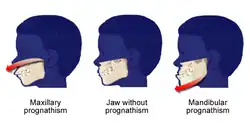

The primary use of surgery to correct jaw disproportion or malocclusion is rare in most countries due to private health insurance and public hospital funding and health access issues. A small number of mostly heavily socialist funded countries report that jaw correction procedures occur in some form or other in about 5% of a general population, but this figure would be at the extreme end of service [3][4][5] presenting with dentofacial deformities like maxillary prognathisms, mandibular prognathisms, open bites, difficulty chewing, difficulty swallowing, temporomandibular joint dysfunction pains, excessive wear of the teeth, and receding chins.

A disproportionately grown upper or lower jaw causes dentofacial deformities. Chewing becomes problematic, and may also cause pain due to straining of the jaw muscle and bone. Deformities range from micrognathia, which is when the mandible does not grow far forward enough (over bite), and when the mandible grows too much, causing an under bite; all of which are uncomfortable. Also, a total maxilla osteotomy is used to treat the "long face syndrome", known as the skeptical open bite, idiopathic long face, hyper divergent face, total maxillary alveolar hyperplasia, and vertical maxillary excess. Prior to surgery, surgeons should take x-rays of the patient's jaw to determine the deformity, and to make a plan of procedures.[11] Mandible osteotomies, or corrective jaw surgeries, benefit individuals who have difficulty chewing, swallowing, TMJ pains, excessive wear of the teeth, open bites, overbites, underbites, or a receding chin. The deformities listed above can be perfected by an osteotomy surgery of either the maxilla or mandible (whichever the deformity calls for), which is performed by an oral surgeon who is specialized in the working with both the upper and lower jaws.[12] Orthognathic surgery is also available as a very successful treatment (90–100%) for obstructive sleep apnea.[13]

Sagittal split osteotomy

This procedure is used to correct mandible retrusion and mandibular prognathism (over and under bite). First, a horizontal cut is made on the inner side of the ramus mandibulae, extending anterally to the anterior portion of the ascending ramus. The cut is then made inferiorly on the ascending ramus to the descending ramus, extending to the lateral border of the mandible in the area between the first and second molar. At this time, a vertical cut is made extending inferior to the body of the mandible, to the inferior border of the mandible. All cuts are made into the middle of the bone, where bone marrow is present. Then, a chisel is inserted into the pre existing cuts and tapped gently in all areas to split the mandible of the left and right side. From here, the mandible can be moved either forwards or backwards. If sliding backwards, the distal segment must be trimmed to provide room in order to slide the mandible backwards. Lastly, the jaw is stabilized using stabilizing screws that are inserted extra-orally. The jaw is then wired shut for approximately 4–5 weeks.[37]

Mandible and maxilla osteotomies date to the 1940s. They were used to correct dentofacial deformities like a malocclusion, and a prognathism.[41] Advances have been made in the procedures, and in the anesthesia used. In 1985, mandible and maxilla osteotomies were effectively used to correct more extreme deformities like receding chins, and to relieve pain from temporomandibular joint disorder (TMJ).